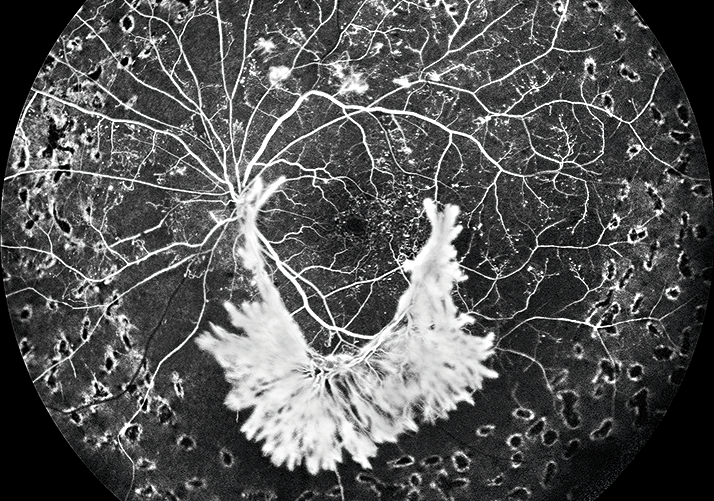

Fluorescein angiography optomap® UWF-image: Coats’ Disease in the far periphery.

Widefield fluorescein angiography is ideal for documenting the complexities of proliferative diabetic retinopathy. It offers the practitioner views into the far peripheral retina where capillary nonperfusion, hemorrhages and neovascularization are often present.

Ultra-widefield fluorescein angiography image demonstrating extensive peripheral changes associated with a retinal vein occlusion including neovascularization, nonperfusion and far peripheral leakage.